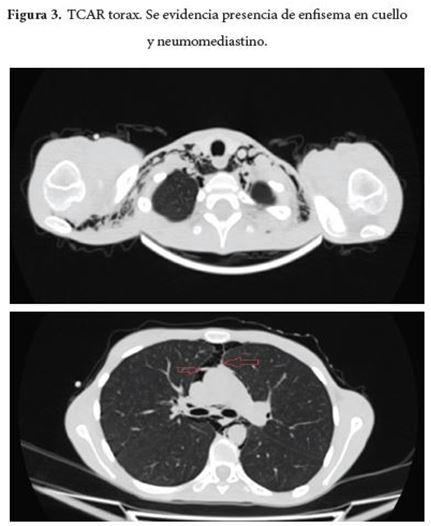

Al día siguiente de su ingreso presenta dolor cervical, sin disnea ni dolor torácico y se advierte presencia de enfisema subcutáneo en cuello y parte superior del tórax con evidencia de enfisema subcutáneo en radiografía de tórax (Figura 1 y 2) y se indica TCAR de tórax (Figura 3) en el cual se halla pneumomediastino sin pneumotórax. La paciente presenta durante días posteriores persistencia de cervicalgia y además asocia dolor torácico, sin disnea ni deterioro del patrón respiratorio ni alteración de las constantes vitales, como dato relevante al examen físico se advierte el signo de Hamman a la auscultación cardiaca. Se le realizan estudios de extensión en busca de la etiología del pneumomediastino con endoscopia de vías digestivas altas que reporta gastropatía eritematosa antrocorporal y fibrobroncoscopia con reporte normal.

La mayoría de los casos probables, se pueden diagnosticar con una historia clínica y examen físico detallados, sumados a los exámenes diagnósticos paraclínicos complementarios (imágenes, estudios endoscópicos, electrocardiograma); y siempre es importante tener una sospecha clínica alta por lo vago de los síntomas y su amplio grupo de enfermedades que son su diagnóstico diferencial. En el enfoque inicial, la radiografía del tórax en proyección frontal y lateral (con una sensibilidad de 89,1%)[14] es la imagen de elección primaria, pues puede detectar más del 90% de los casos. Los signos radiológicos incluyen el signo de la vela por elevación del timo especialmente en la edad pediátrica; el signo del anillo por aire circundante a la arteria pulmonar o sus ramas, en especial cuando se rodea el segmento intramediastinal de la arteria pulmonar derecha. Si el diagnostico se puede realizar con la radiografía de tórax no se necesitan exámenes adicionales. La tomografía de tórax es más específica y detecta lesiones más pequeñas, se utiliza principalmente para el estudio de patología pulmonar subyacente y cuando no se detectan alteraciones en la radiografía de tórax o esta es no concluyente. Las pruebas adicionales como el esofagograma, la esofagoscopia y la broncoscopia solo están indicados en aquellos pacientes en los que se sospeche un origen secundario. Algunos autores sugieren que solo deberían realizarse si el paciente presenta disfagia, vomito, trauma previo, fiebre, leucocitosis, derrame pleural, pneumoperitoneo y enfermedad gastrointestinal[15].